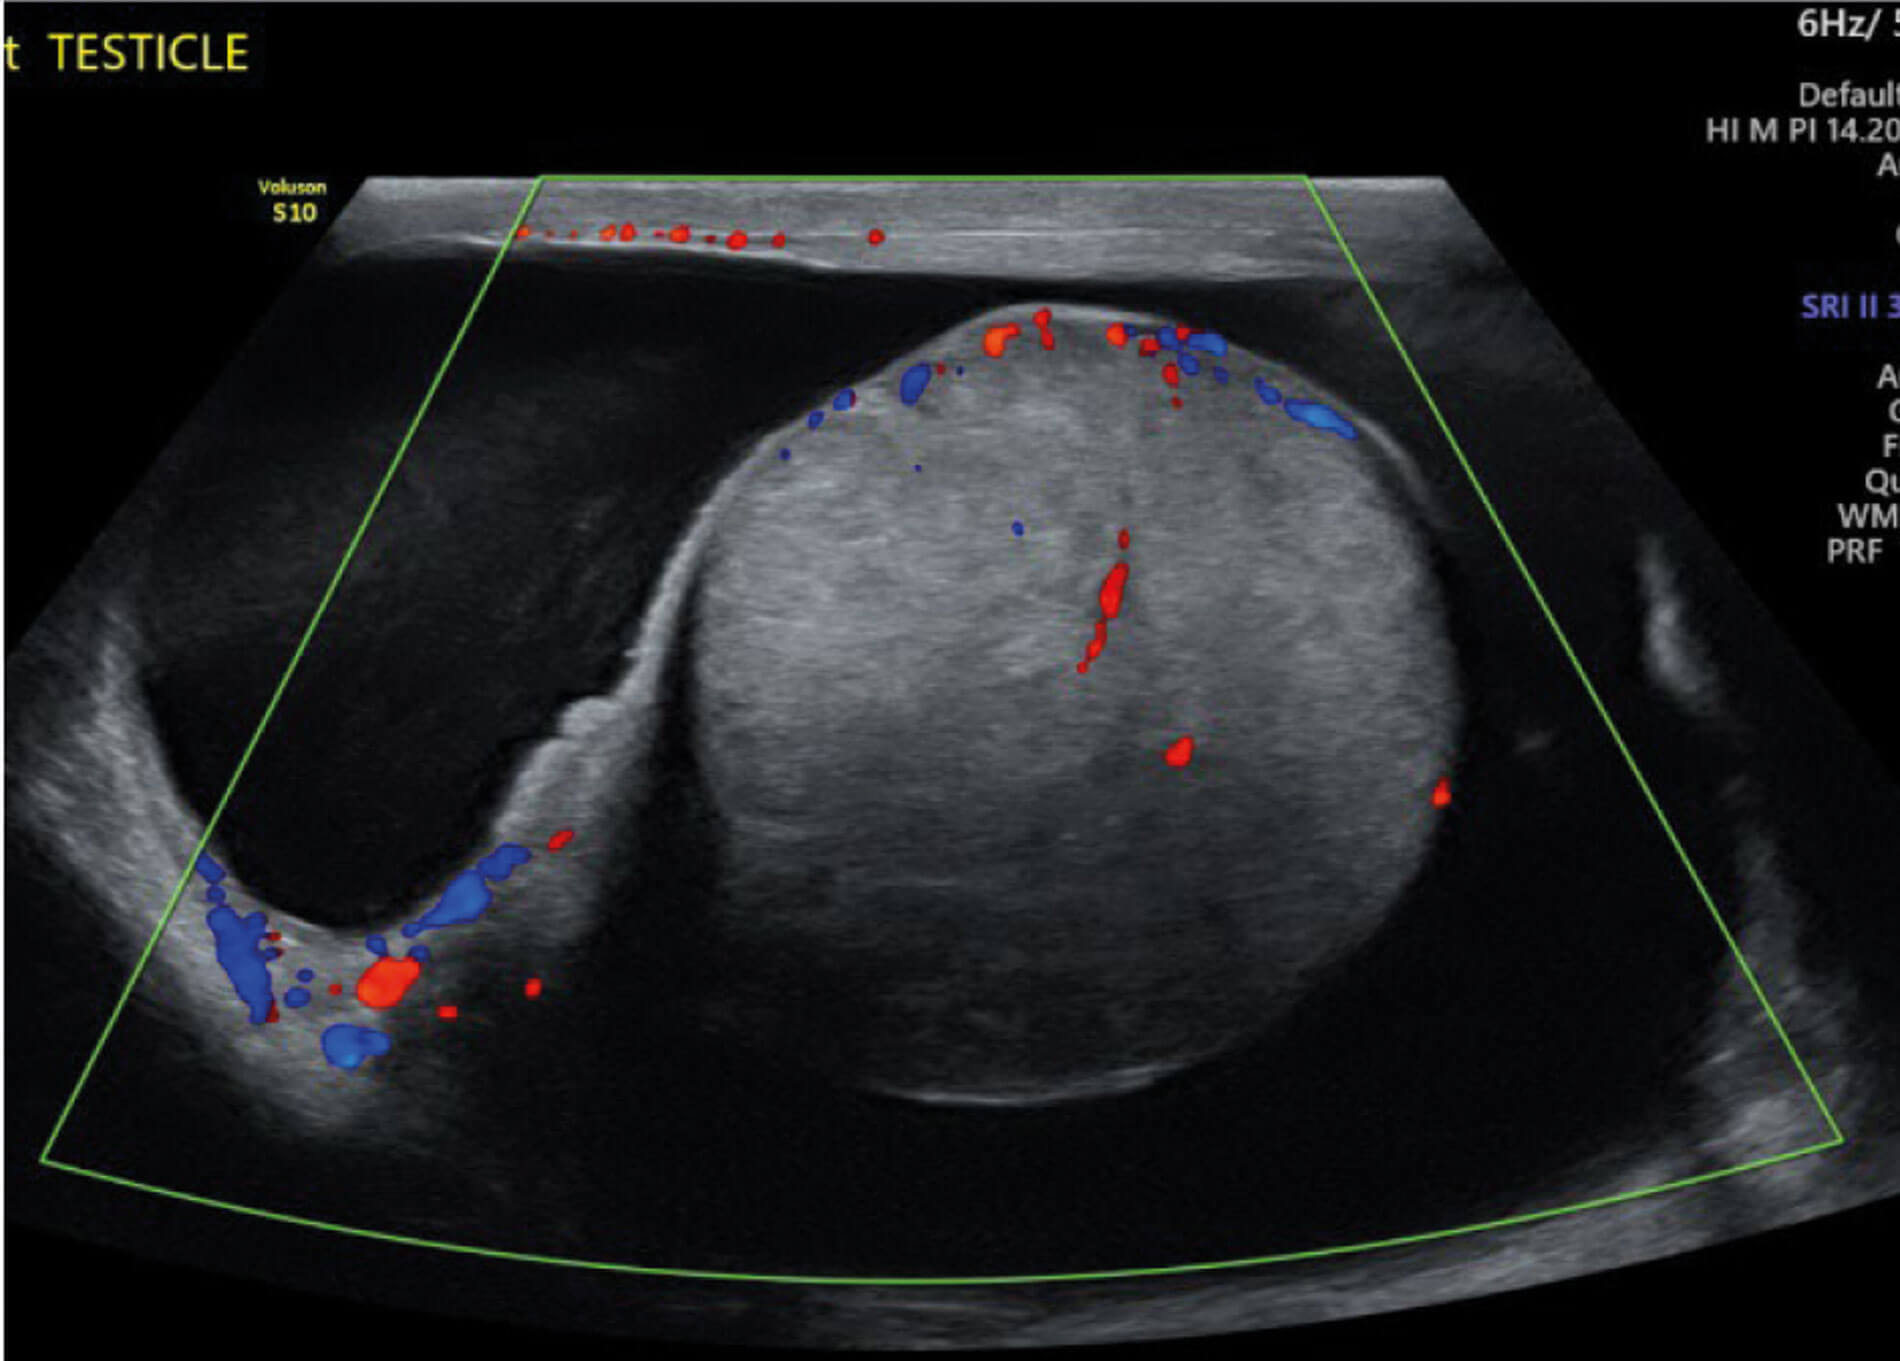

He sought a second opinion from our hospital. A further ultrasound was performed and images were compared. This confirmed a solitary right testis infiltrated by a poorly defined mass of mixed echogenicity. The mass also showed increased vascularity. There was a surrounding hydrocele measuring 100ml with an empty left hemiscrotum.

Figure 4: US in November 2021.